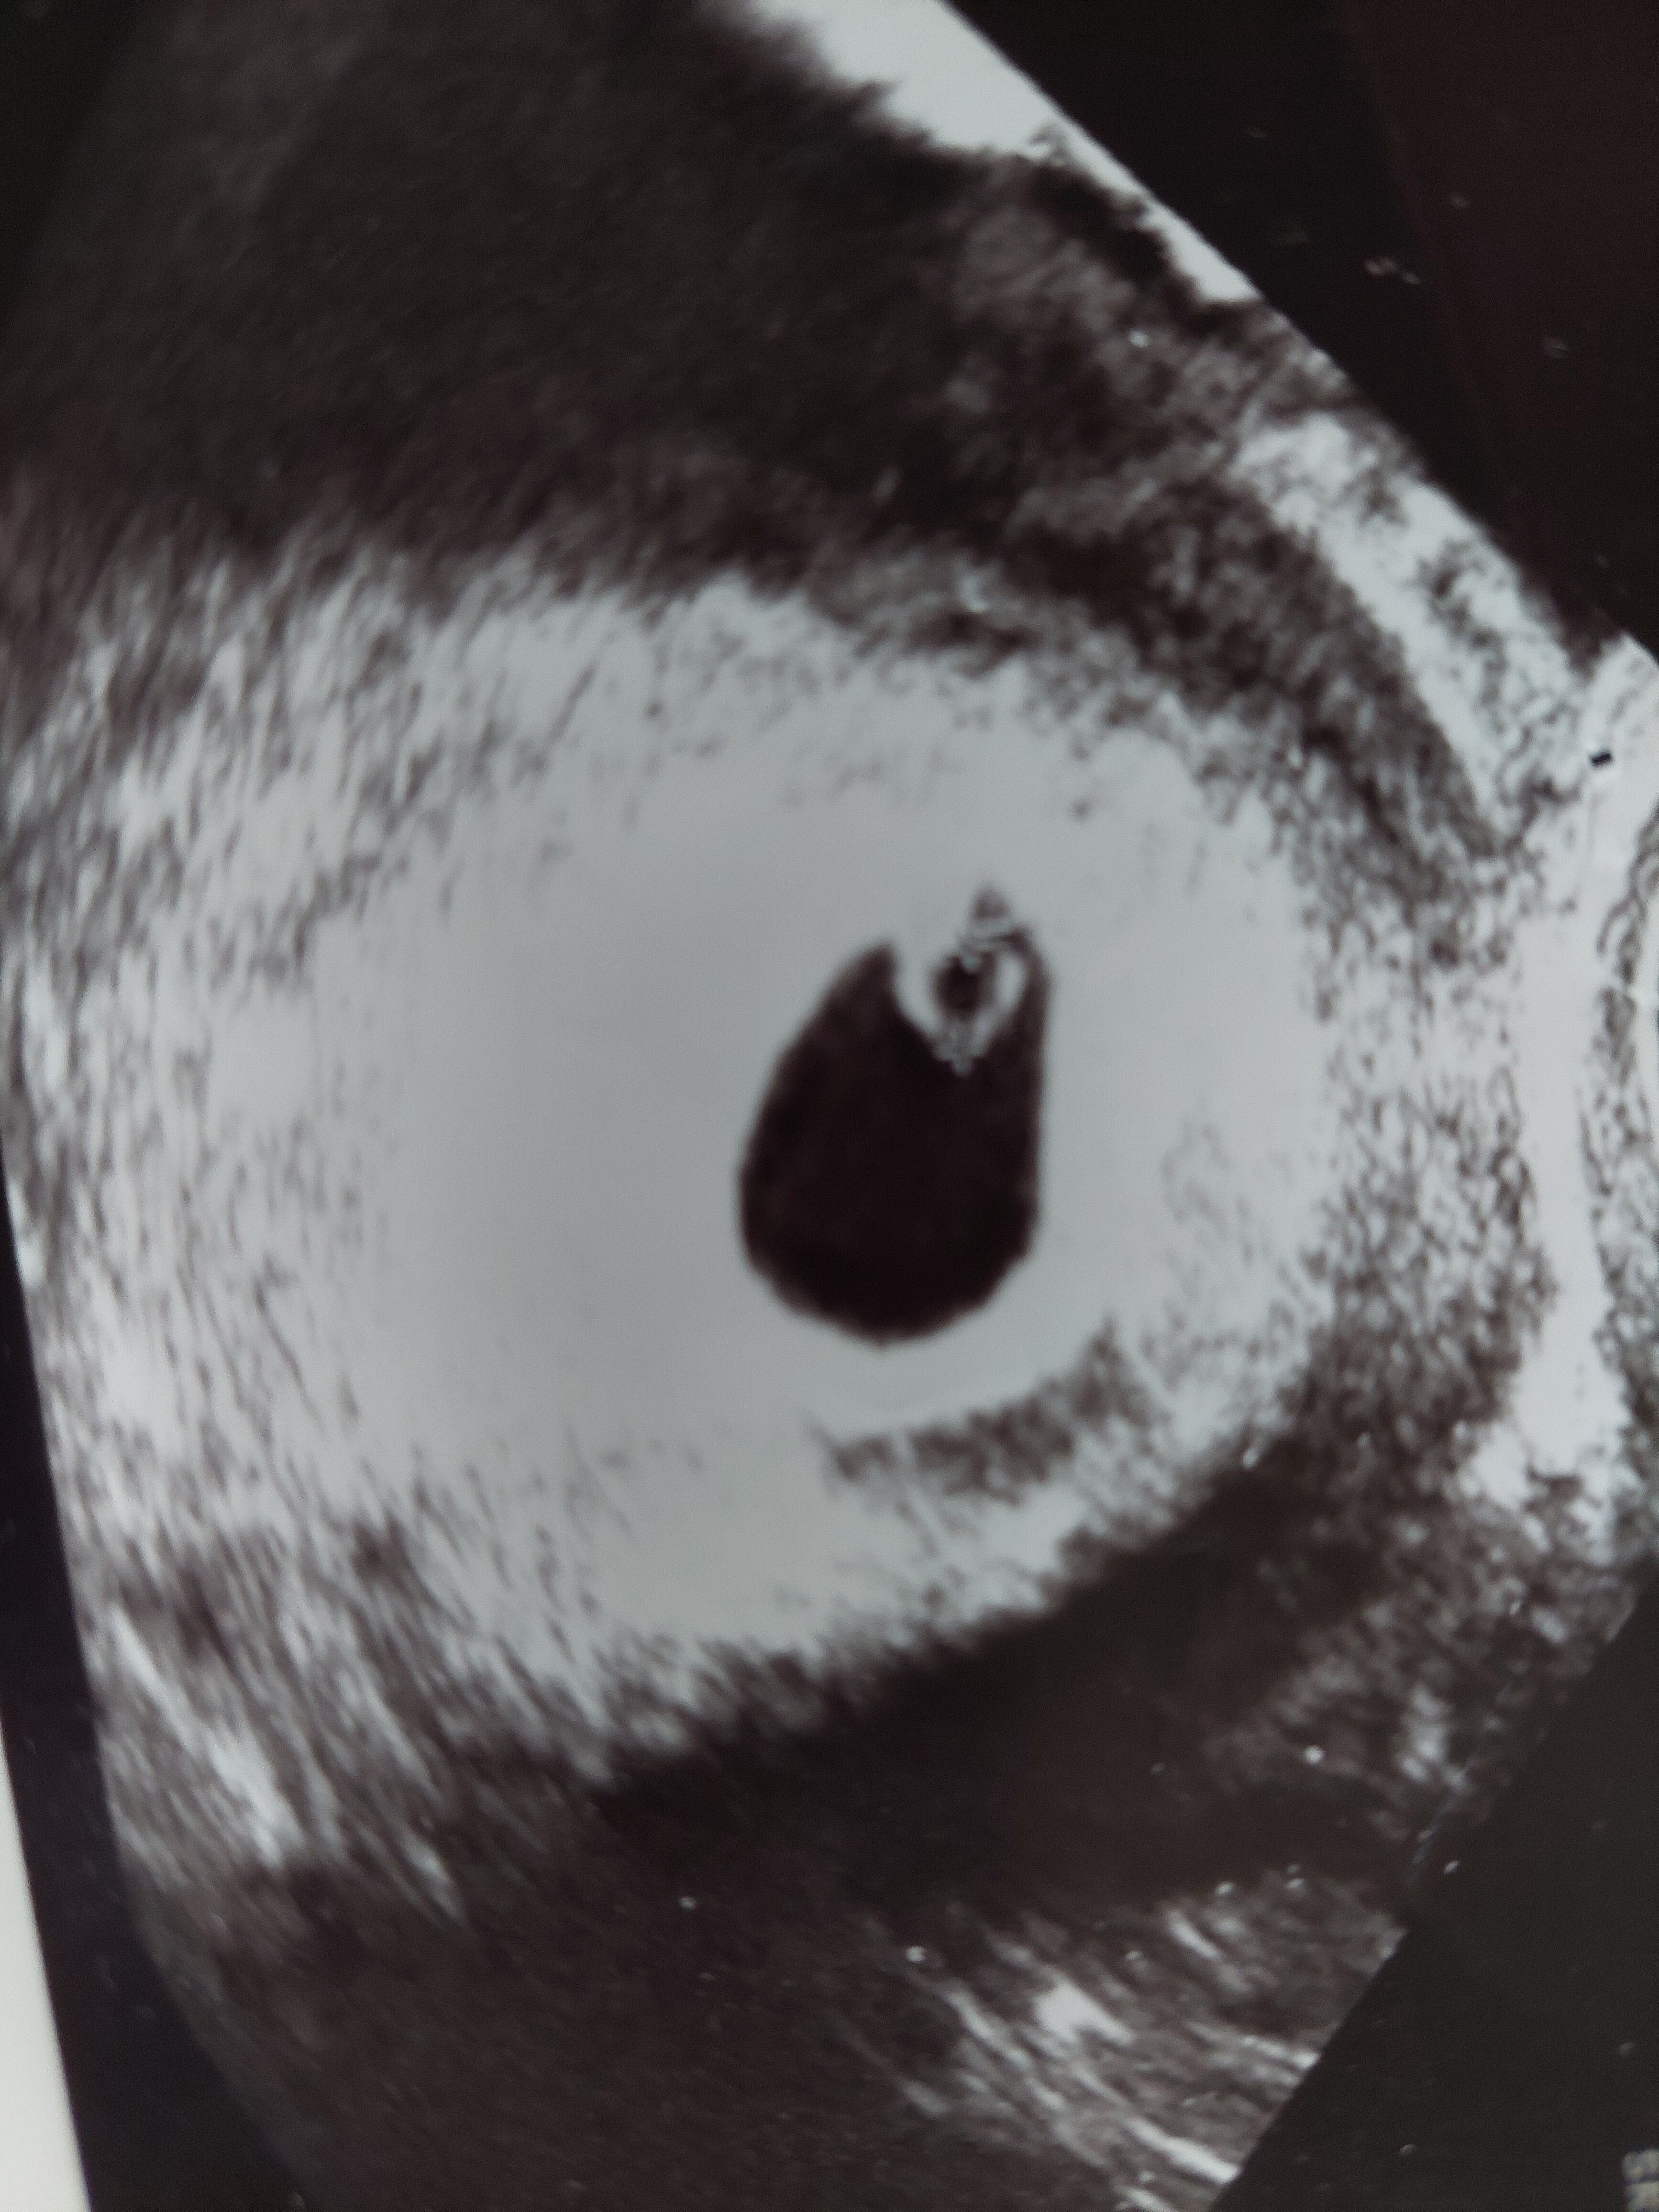

A ja wczoraj byłam zadowolona z wizyty, ale dzisiaj już panikuję. Jakoś nie podobał mi się ten pęcherzyk żółtkowy, pytałam wczoraj czy nie jest za duży, albo czy ciążowy nie jest za mały. Nie mówiła, że jest coś nie tak, ale naczytałam się, że za duży pęcherzyk ciążowy nie wróży dobrze i nie znalazłam żadnej pozytywnej historii. Jestem albo głupia, albo nie wiem co.

W poniedziałek idę jeszcze na NFZ po skierowanie na badania, ale chyba sprawdzę jeszcze USG czy pęcherzyki urosły,czy zarodek rośnie w ogóle. Macie jakieś zdjęcie USG z poprzednich ciąży z 5-6 tygodnia? Bo już przeglądałam swoje, ale wydaje mi się,że tak dużego pęcherzyka żółtkowego nie miałam, a teraz ginka w sumie nie mierzyła nic poza zarodkiem.

W 5+5 pęcherzyk 15mm, żółtko 3,2mm, zarodek 2,5mm, widać pulsowanie.

A teraz w 5+2/5+3 byl pusty pecherzyk 12mm.